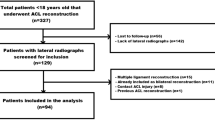

Inclusion criteria were: isolated single-bundle hamstring autograft ACL reconstruction within 8 weeks of contact or non-contact ACL injury, standard in-house MRI assessment, clinical evaluation by the senior surgeon under anaesthesia, and a completed 1-year follow-up. Exclusion criteria were combined ACL/ALC reconstruction, age < 18 or > 45 years, previous surgery or symptoms in the affected knee, partial ACL tear, previous or current ACL injury on the contra-lateral leg, multi-ligament damage with an indication for additional surgical intervention, extensive cartilage damage (Outerbridge > III), clinically excessive varus/valgus leg axis, and meniscus tears treated with fixation and, therefore, interfering with the rehabilitation protocol (Fig. 1). Diagnosis of meniscal tears as well as accessibility and necessity of fixation required arthroscopic confirmation. Patients who underwent partial meniscectomy were included in the study.